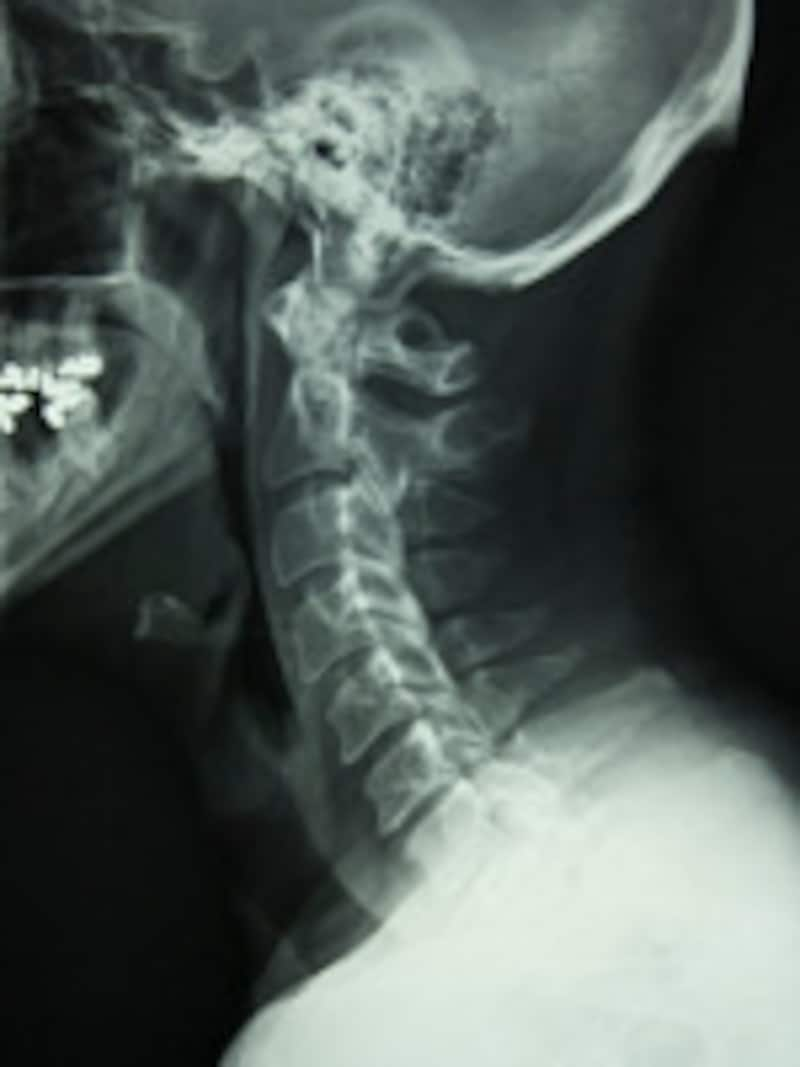

![]() |

| レントゲン写真を見ると、首の骨はC字状にカーブしています |

健康な人の首の骨は、横から見ると 「C」 字状にカーブしています。ところが枕が低すぎると、首の骨の自然なカーブがなくなり、首の痛みや肩こりが起こります。また、頭が心臓より低い位置になるので、頭や顔の血液の循環が悪くなります。そのため、朝に顔がむくみやすくなります。

仰向けに寝て、額と鼻の先端を結んだ線が床に対して5度のとき、首のカーブは立っている状態と同じになります。ですから、この寝姿を保てる枕が良い枕ということになります。

この枕をして仰向けでレントゲンを撮ると、首の骨が水平面に対して約15度の角度になっているのがポイントです。理想的な高さの枕を使うと、肩こりや頭痛、首の痛みが軽くなるだけでなく、頚椎の中にある神経の通り道が広がっていることが、MRI検査で実証されています。